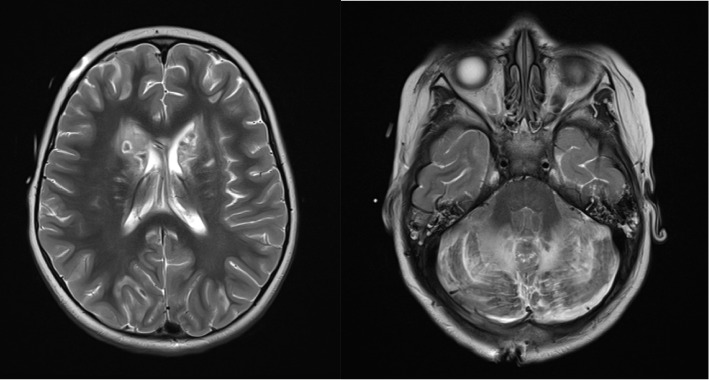

美沙酮是一种用于治疗疼痛和阿片类药物依赖的合成阿片类药物。尽管它的好处,意外摄入美沙酮在儿科患者可导致显著的发病率和死亡率。儿童摄入美沙酮引起的急性毒性包括脑白质病和小脑炎。对儿童美沙酮过量后的治疗和影响临床结果的因素的研究有限。我们报告一个3岁的儿童严重脑损伤和死亡后意外摄入美沙酮。我们的病例是独特的,因为我们能够获得摄取后的血清美沙酮水平,这是用来指导干预和治疗。通过这个案例,我们的目的是促进对美沙酮毒性的日益了解,同时也倡导实施保护我们儿科人口的政策。

Methadone is a synthetic opioid used to treat pain and opioid dependence. Despite its benefits, accidental ingestion of methadone in pediatric patients can lead to significant morbidity and mortality. Documented findings of acute toxicity secondary to methadone ingestion in children include leukoencephalopathy and cerebellitis. There is limited research into treatment and factors influencing clinical outcomes following methadone overdose in children. We report a 3-year-old child with severe brain injury and death following accidental ingestion of methadone. Our case is unique in that we were able to acquire a serum methadone level following ingestion, which was used to guide intervention and treatments. Using this case, we aim to contribute to the growing understanding of methadone toxicity while also advocating for the implementation of policies that protect our pediatric population.